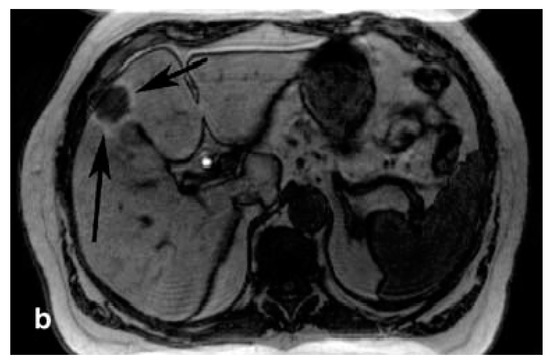

- Vogl, T.J.; Hamm, B.; Schnell, B.; Eibl-Eibesfeldt, B.; Steiner, S.; Lissner, J. The clinical value of Mn-DPDP: A new paramagnetic hepatobiliary contrast medium for magnetic resonance tomography of the liver. Fortschr. Röntgenstr. 1991, 155, 568–574. [Google Scholar] [CrossRef] [PubMed]

- Reimer, P.; Schneider, G.; Schima, W. Hepatobiliary contrast agents for contrast-enhanced MRI of the liver: Properties, clinical development and applications. Eur. Radiol. 2004, 14, 559–578. [Google Scholar] [CrossRef] [PubMed]

- Rummeny, E.J.; Torres, C.G.; Kurdziel, J.C.; Nilsen, G.; Op de Beeck, B.; Lundby, B. MnDPDP for MR imaging of the liver. Results of an independent image evaluation of the european phase III studies. Acta Radiol. 1997, 38, 638–642. [Google Scholar] [PubMed]

- Rummeny, E.; Ehrenheim, C.; Gehl, H.B.; Hamm, B.; Laniado, M.; Lodemann, K.P.; Schmiedel, E.; Steudel, A.; Vogl, T.G. Manganese-DPDP as a hepatobiliary contrast agent in the magnetic resonance imaging of liver tumors. Results of clinical phase II trials in germany including 141 patients. Investig. Radiol. 1991, 26. [Google Scholar] [CrossRef] [PubMed]

- Sahani, D.V.; O’Malley, M.E.; Bhat, S.; Hahn, P.F.; Saini, S. Contrast-enhanced MRI of the liver with mangafodipir trisodium: Imaging technique and results. J. Comput. Assist. Tomogr. 2002, 26, 216–222. [Google Scholar] [CrossRef] [PubMed]